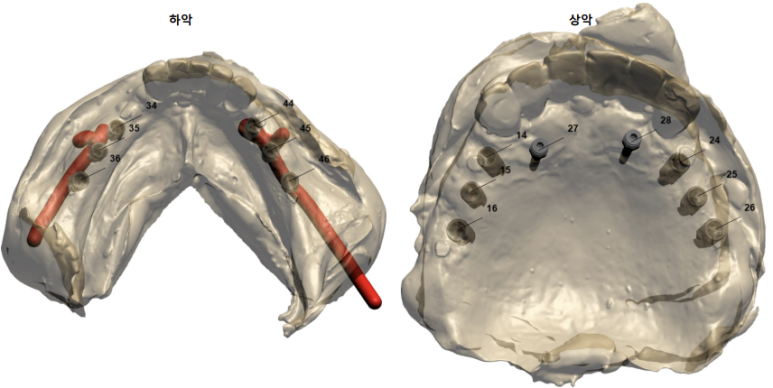

오스템 임플란트의 네비게이션 임플란트 시스템.

원가이드를 활용하여 위턱부터 임플란트 수술!

저희 치과에서는 적극적으로 네비게이션 임플란트 시스템을 활용하고 있습니다.

솔직히 임플란트 2-3개 정도는 보조 Tool 없이 해낼 수 있어야 한다고 생각하지만, 이렇게 임플란트 개수가 많아지면 아무래도 술자의 피로도를 줄여주며 보다 정확한 시술을 가능하게 해주는 Tool 이 필요하거든요,

아무래도 여러개의, 특히 위아래 어금니가 모두 없는 케이스다 보니 정밀하게 임플란트 방향을 잡기 위해 오스템임프란트의 네비게이션 시스템을 이용하는 것이 술자-환자 모두에게 큰 도움이 됩니다.

환자로써 모든 것을 이해하실 필요까진 없으시다고 생각합니다만.. 대략 이런 식으로 CT 상에서 완성될 크라운을 먼저 배열하고 역산하여 임플란트 위치를 정합니다.

그리고 이 위치를 그대로 옮길 수 있는 수술 장치를 만들어서 입안에 장착하고 수술을 받으시는 것이죠.

양쪽 위 어금니 부위에 깔끔하게 3개씩 임플란트를 심어드렸습니다.

이 3개의 임플란트는 시간이 흘러 첫번째, 두번째 작은 어금니 그리고 첫번째 큰 어금니가 됩니다.

원가이드를 활용하여 2주 후 아래턱 임플란트 수술!

약 2주 후 아래턱 임플란트 수술을 시행하였습니다.